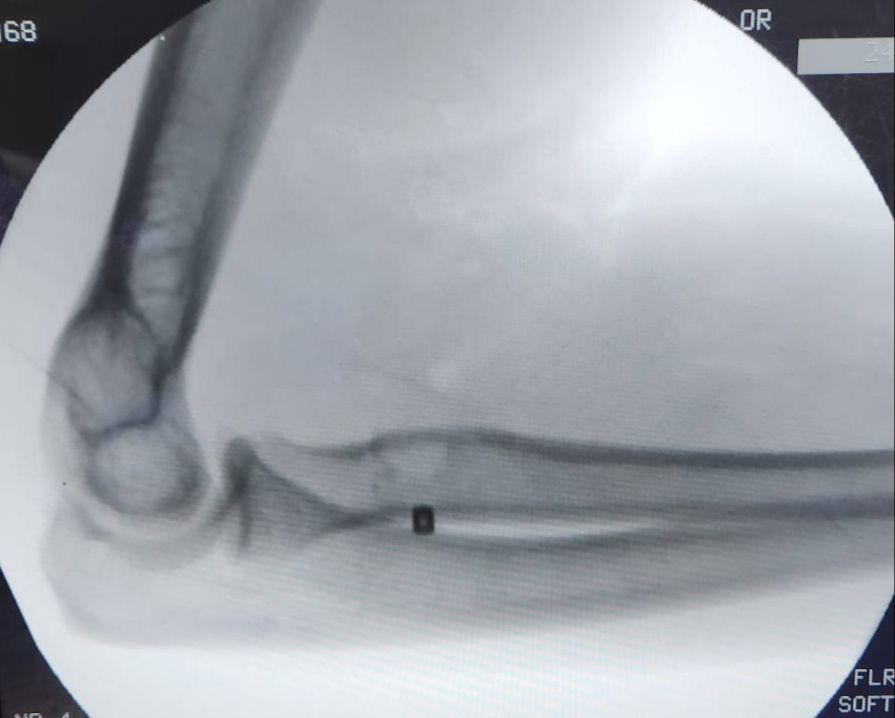

تمكن فريق طبي في جراحة العظام بمستشفى الملك فهد بجدة من إجراء عملية لمريض في الأربعين من عمره ، و إعادة وتره المقطوع ، نتيجة لتعرضه قبل شهر لقطع في العضلة التي تسمى البايسيبس ، و قد تمكن الفريق من إعادة و تثبيت الوتر المقطوع لمكانه بقيادة الدكتور شهاب بوسطجي استشاري الزمالة الألمانية في جراحة العظام و إصابة الملاعب بمستشفى الملك فهد بجدة .

و أشار الدكتور بوسطجي رئيس الفريق الطبي الذي أجرى العملية أنه قد تم إجراء الفحوصات اللازمة للمريض قبل العملية  من أشعة رنين مغناطيسي ، مضيفاً إلى أن هذا النوع من العمليات يُعد نادراً و من العمليات الدقيقة جداً التي تحتاج وقتاً للعودة لوضعها الطبيعي .